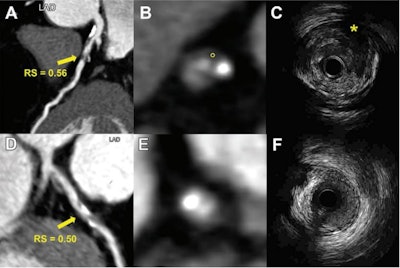

Chen and colleagues wanted to explore whether a radiomic signature based on CCTA features could detect vulnerable plaques, as well as see whether these plaques are tied to risk for future major adverse cardiac events. They used intravascular ultrasound as the reference standard for their model.

The radiomic signature development data included patients first undergoing CCTA and then intravascular ultrasound within three months between 2013 and 2020 at one hospital. In total, the researchers included 419 lesions from 225 patients with an average age of 64. The model used 16 radiomic features, including two shape features and 14 textural features for its development.

Chen and colleagues reported that the model achieved the following area under the curve (AUC) values: training set, 0.81; validation set, 0.75; internal test set, 0.80; and external test set, 0.77. The investigators also found that a high radiomic signature of greater than or equal to 1.07 was independently tied to major adverse cardiac events over a median three-year follow-up period (hazard ratio, 2.01; p = 0.005).